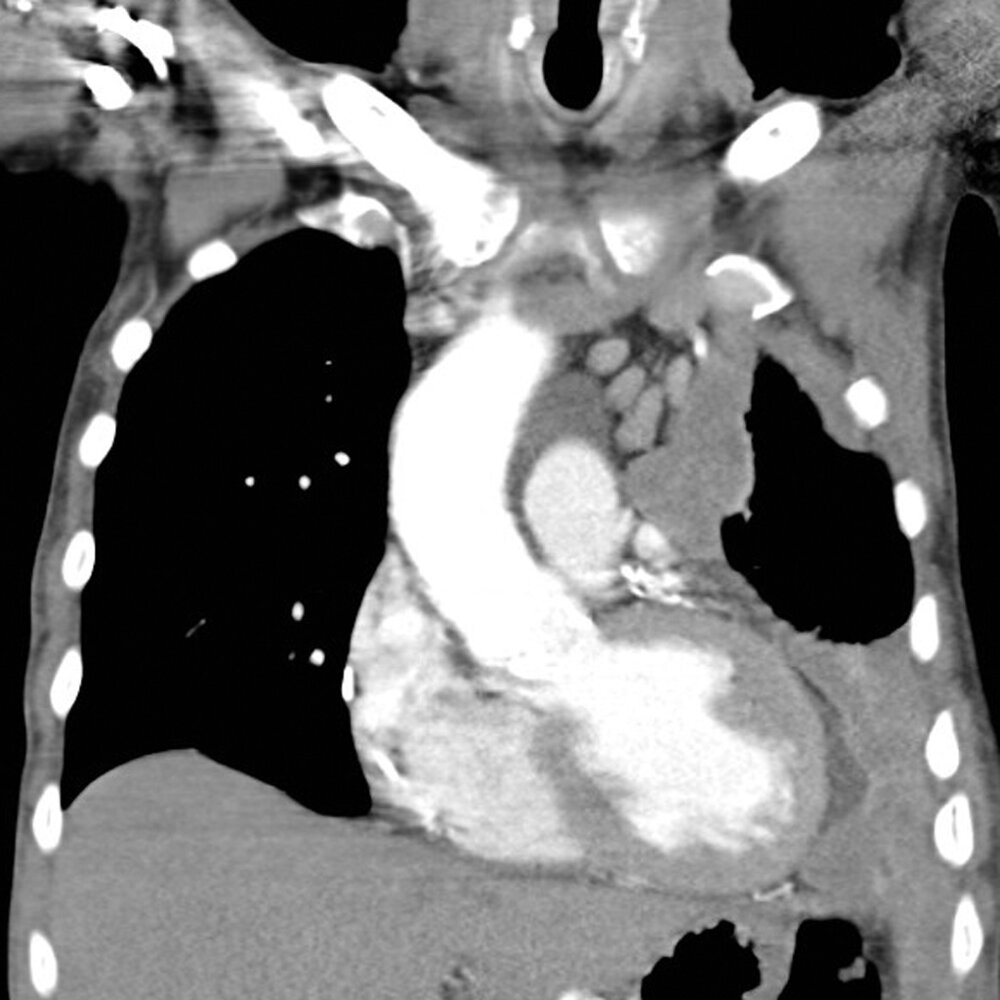

Initial imaging

• Modalities

• Chest x-ray: often routinely obtained first

• Contrast-enhanced CT: most sensitive imaging modality for diagnosis

• Findings in pleural mesothelioma

• Multiple nodular pleural lesions (pleural thickening)

• Pleural effusion

• Thickening of interlobar fissures

• Pleural opacities (calcifications or plaques)

• Signs of local tumor growth, e.g., reduced size of ipsilaterallung fields, mediastinal shift

• Signs of local invasiveness, e.g., obliteration of fat planes